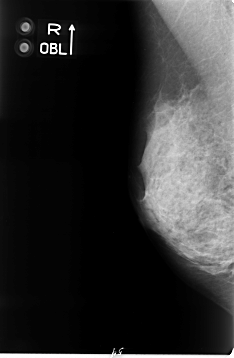

B_3062_1.RIGHT_MLO

RIGHT_CC LINES 4672 PIXELS_PER_LINE 2896 BITS_PER_PIXEL 12 RESOLUTION 50 NON_OVERLAY

RIGHT_MLO LINES 4648 PIXELS_PER_LINE 3032 BITS_PER_PIXEL 12 RESOLUTION 50 NON_OVERLAY